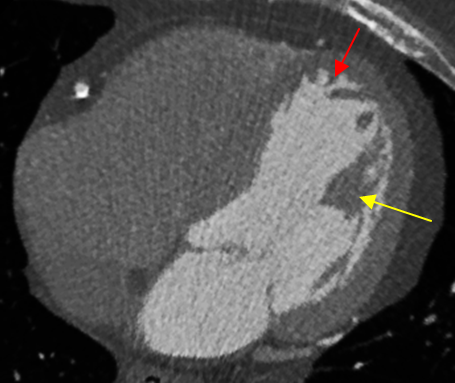

Figure 1: Left ventricular trabeculae carneae (pointed by the red arrow) and papillary muscles (pointed by the yellow arrow) can be clearly seen in the CTCA images acquired using a 320-MDCT scanner.

Computed Tomography Coronary Angiography (CTCA) is a non-invasive imaging technique that allows for robust quantification of vascular morphology and has the potential for characterizing the atherosclerotic plaque composition [21]. When performed using a 320-Multirow-Detector Computed Tomography (MDCT) scanner, a CTCA scan can be performed within a single heart beat, yielding images with an isotropic spatial resolution of 0.5 mm in a volumetric fashion. The resulting images, in addition to providing vascular morphology information, are capable of providing significant details about the left ventricular (LV) endocardial surface structure. The CTCA images, backed by anatomical studies, have revealed that, instead of a simple and smooth surface, the LV endocardial surface is composed of a complex structure of trabeculae carneae, which are small muscular columns that arise naturally from the inner surface of the ventricles (Figure 1). Also revealed in the CTCA images are the papillary muscles which are attached to the cusps of the atrioventricular (i.e., the mitral and tricuspid) valves (Figure 1).